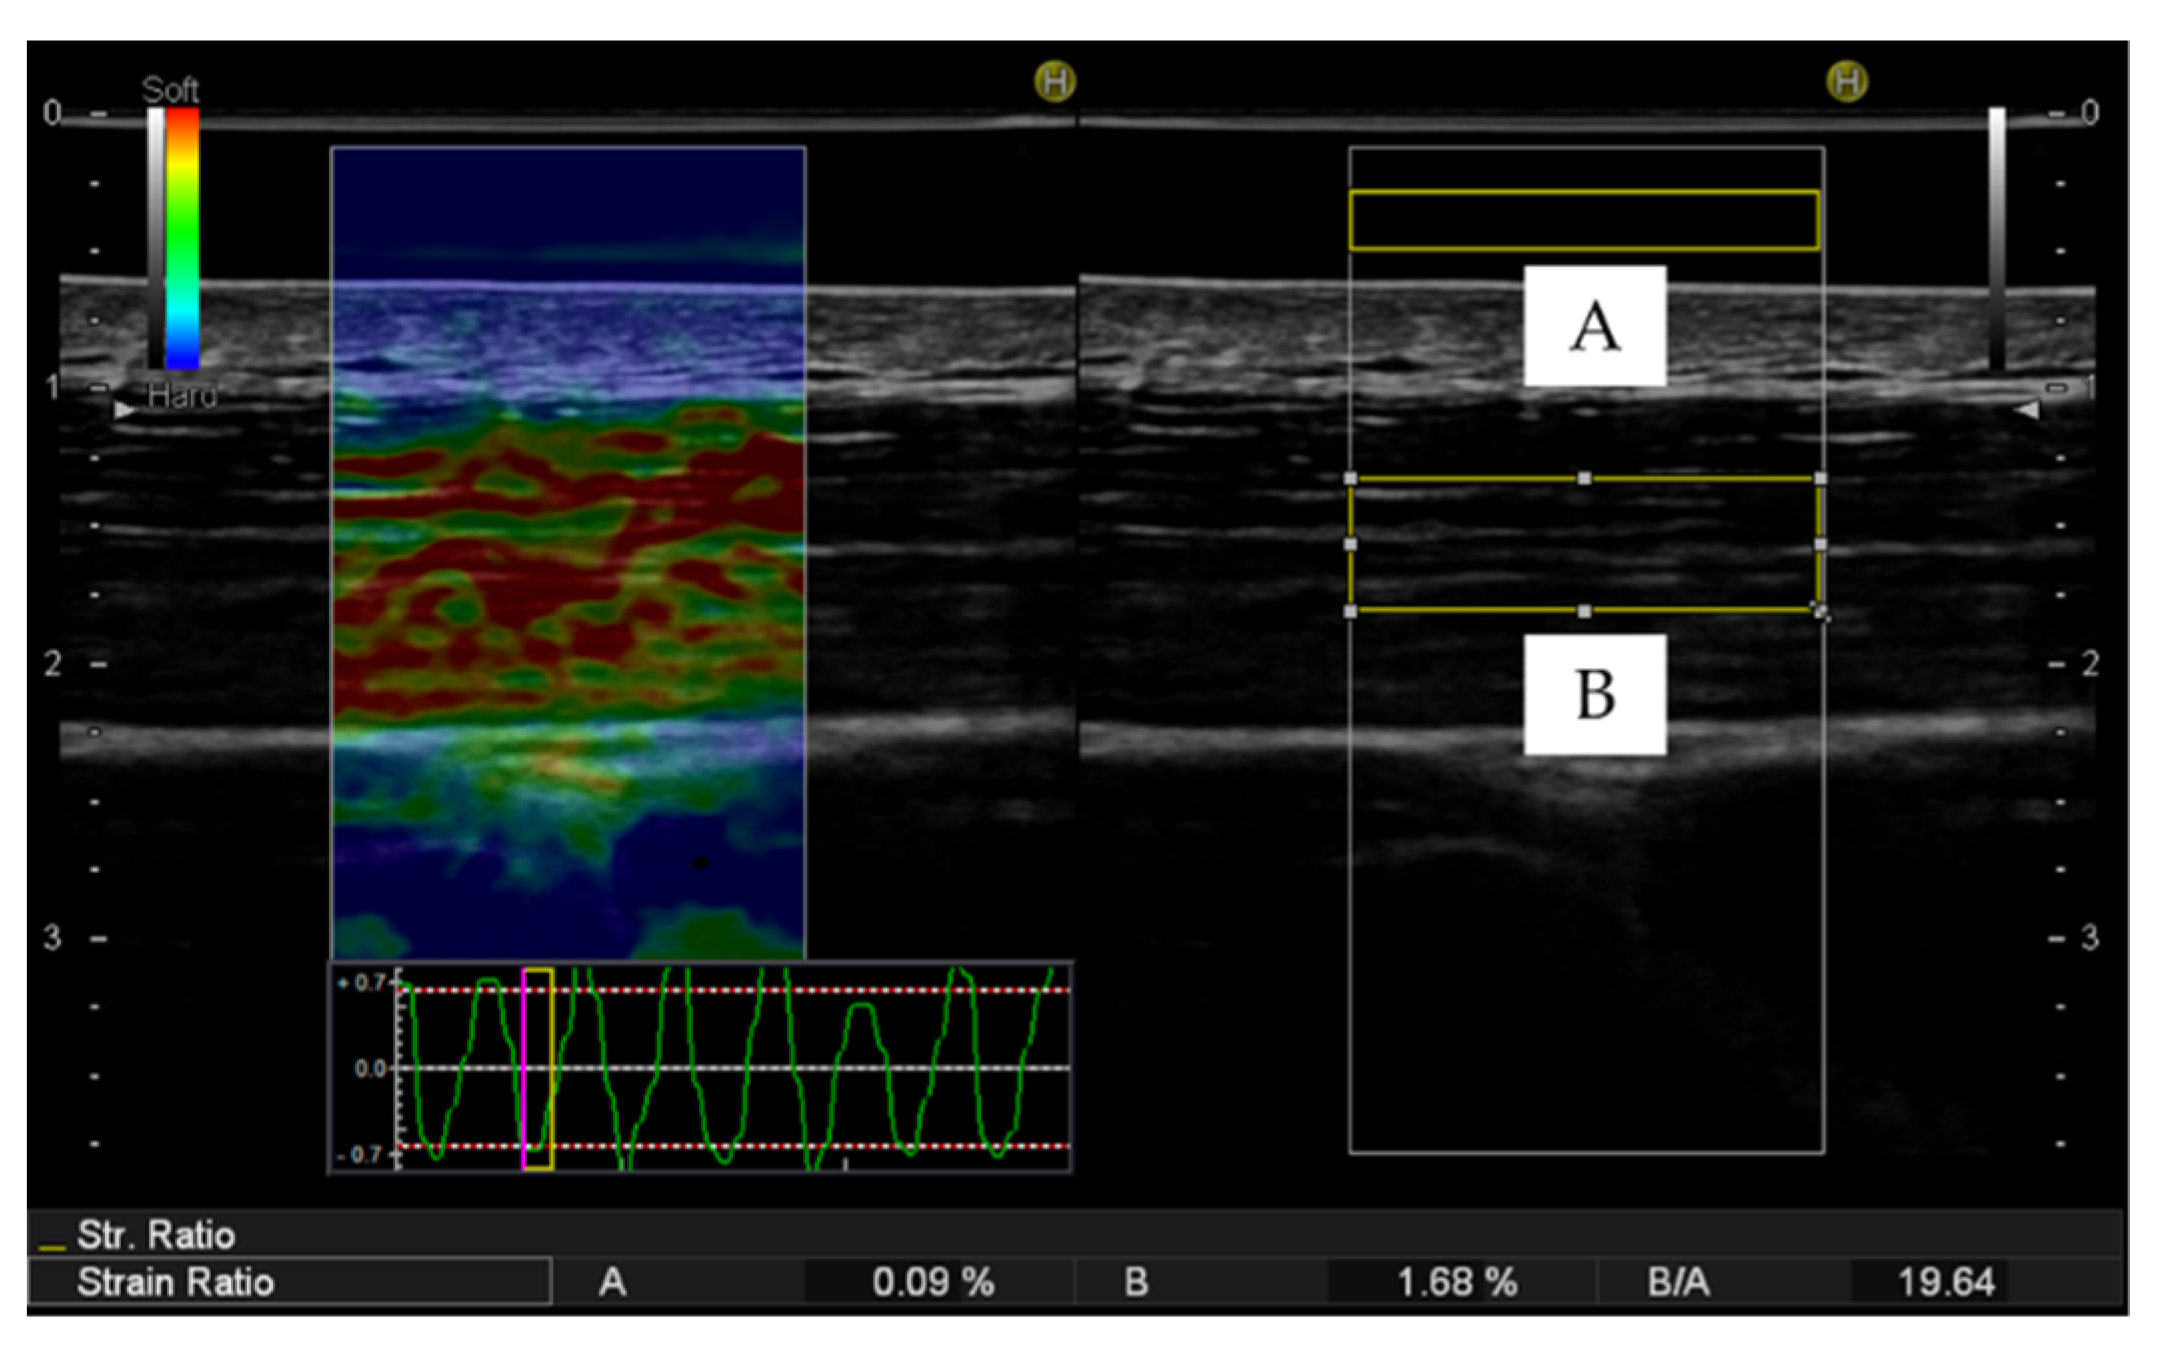

2.3.2. Ultrasound Strain Elastography

- Inami, T.; Tsujimura, T.; Shimizu, T.; Watanabe, T.; Lau, W.Y.; Nosaka, K. Relationship between isometric contraction intensity and muscle hardness assessed by ultrasound strain elastography. Eur. J. Appl. Physiol. 2017, 117, 843–852. [Google Scholar] [CrossRef] [PubMed]